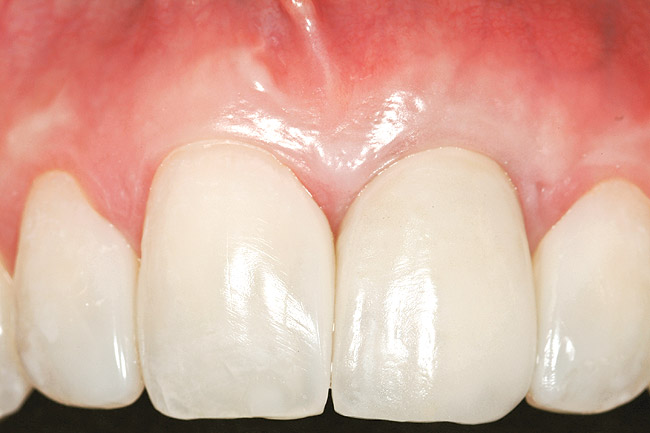

Figure 1  Case One Pretreatment clinical view, Case 1, maxillary right.

Figure 1

A 54-year-old non-smoking woman presented for correction of deep-wide gingival recession in the maxillary anterior (Figure 1 through Figure 3). The patient’s desires were to correct the gingival recession, balance the heights of contour of the tissues, and possibly undergo esthetic enhancement of the maxillary anterior with veneer restorations.

The 2-month postoperative view can be seen in Figure 13 through 15. Note the color match of the tissue, balance of the facial heights of contour, and zones of attached keratinized tissue present.